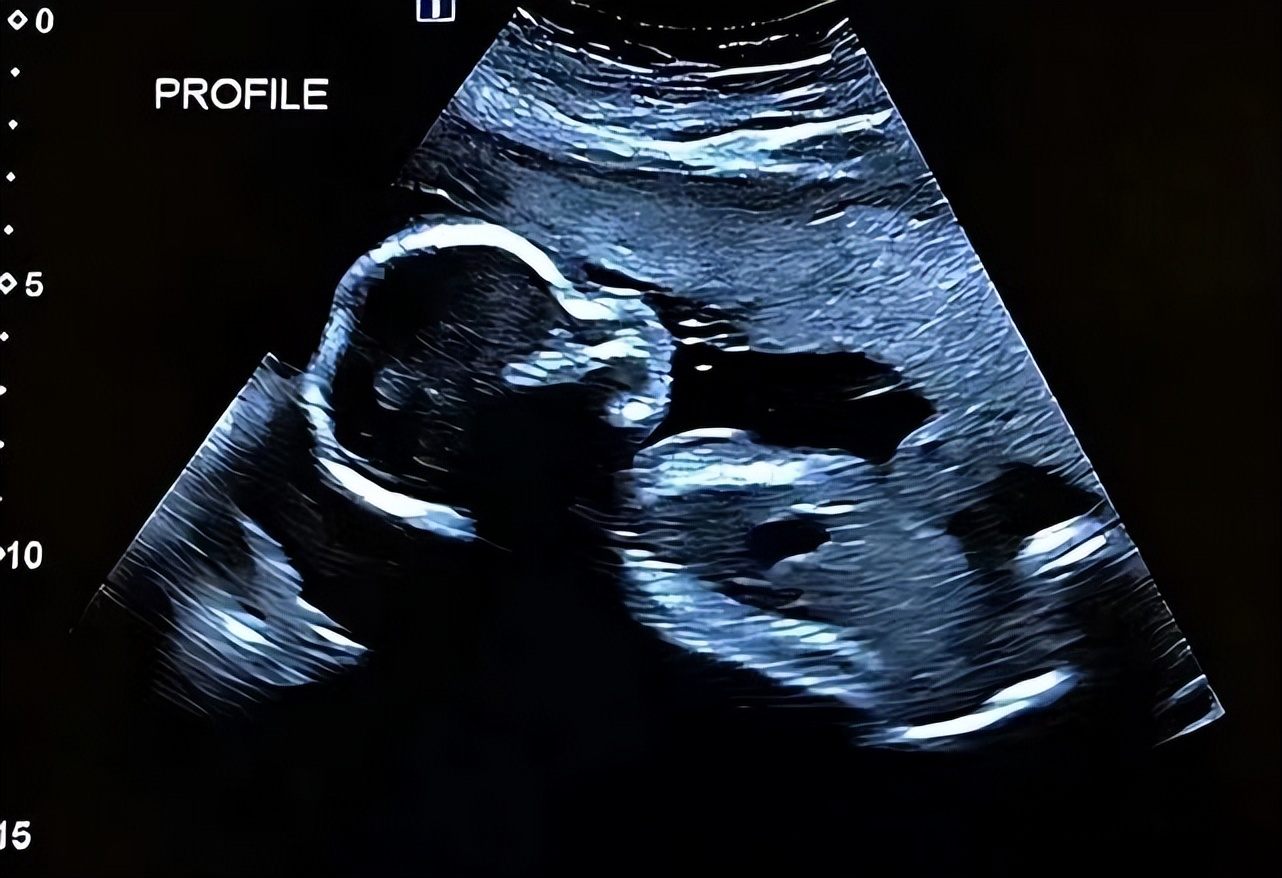

(胎儿影像)

经过检查,医生告诉刘兴莲,

她肚子里的胎儿看上去偏小,

建议她去大医院做个深入的检查。